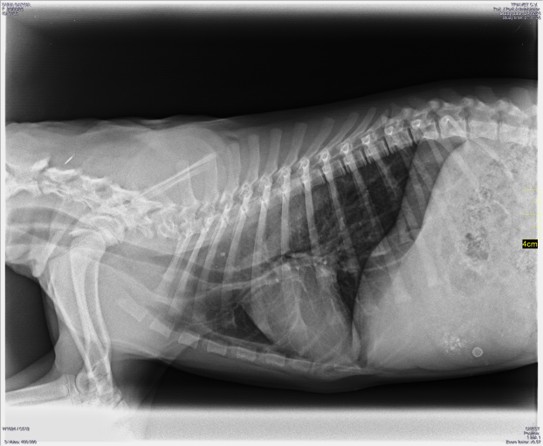

Les radiografies del 29/12/2025: el moment en què el relat canvia

El 29 de desembre de 2025 li van fer radiografies (RX). Recordo aquell dia amb una nitidesa estranya: el pas d’estar preocupat a estar seriosament preocupat. Quan la veterinària decideix que cal imatge, la cosa deixa de ser “observació” i passa a ser “veure què hi ha”.

El resultat va apuntar a una paraula que jo no havia necessitat tenir al meu vocabulari fins llavors: megaesòfag.

Simplificant (de manera superficial), el megaesòfag és un problema de motilitat: l’esòfag no impulsa el menjar cap a l’estómac com hauria de fer. El menjar pot quedar-se retingut, acumular-se i tornar… però no com un vòmit digestiu “típic”, sinó com una regurgitació que pot ser silenciosa i traïdora. I el risc que ho torna realment greu és l’aspiració: que el contingut acabi a les vies respiratòries i provoqui pneumònia per aspiració.

A partir d’aquí, el teu cervell canvia de pantalla. Ja no és “com ho ajustem perquè mengi millor?”. És “quin risc estem gestionant i quina vida implica això?”. La diferència és enorme.